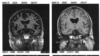

پژوهشگران آمریکایی و آلمانی می‌گویند با استفاده از واکسنِ آزمایشی بیماری آلزایمر توانسته‌اند بخشی از حافظه از دست رفته را در موش‌های آزمایشگاهی احیا کنند. این گام مهمی در تولید واکسن آلزایمر تلقی می‌شود و راه را برای آزمایش‌های بالینی آن در مورد انسان هموار می‌کند.

این واکسن به دستگاه ایمنی بدن می‌آموزد تا با ذرات چسبنده پروتئین آمیلوئید بتا که در مغز افراد مبتلا به زوال عقل جمع شده است و از تماس بین یاخته‌های عصبی جلوگیری می‌کند، مقابله کند.

در این پژوهش جدید دانشمندان کشف کرده‌اند که پروتئین‌ها در ناحیه مغز افراد مبتلا به زوال عقل ساختاری شبیه سنجاق سر می‌سازند که گونه بسیار خطرناکی از آمیلوئید است.

تزریق این واکسن آزمایشی به موش‌ها باعث ترشح پادتن، تقویت سوخت‌وساز گلوکوز در مغز، معکوس شدن روند فراموشی و جلوگیری از شکل‌گیری لخته‌ای آمیلوئید بتا شد.